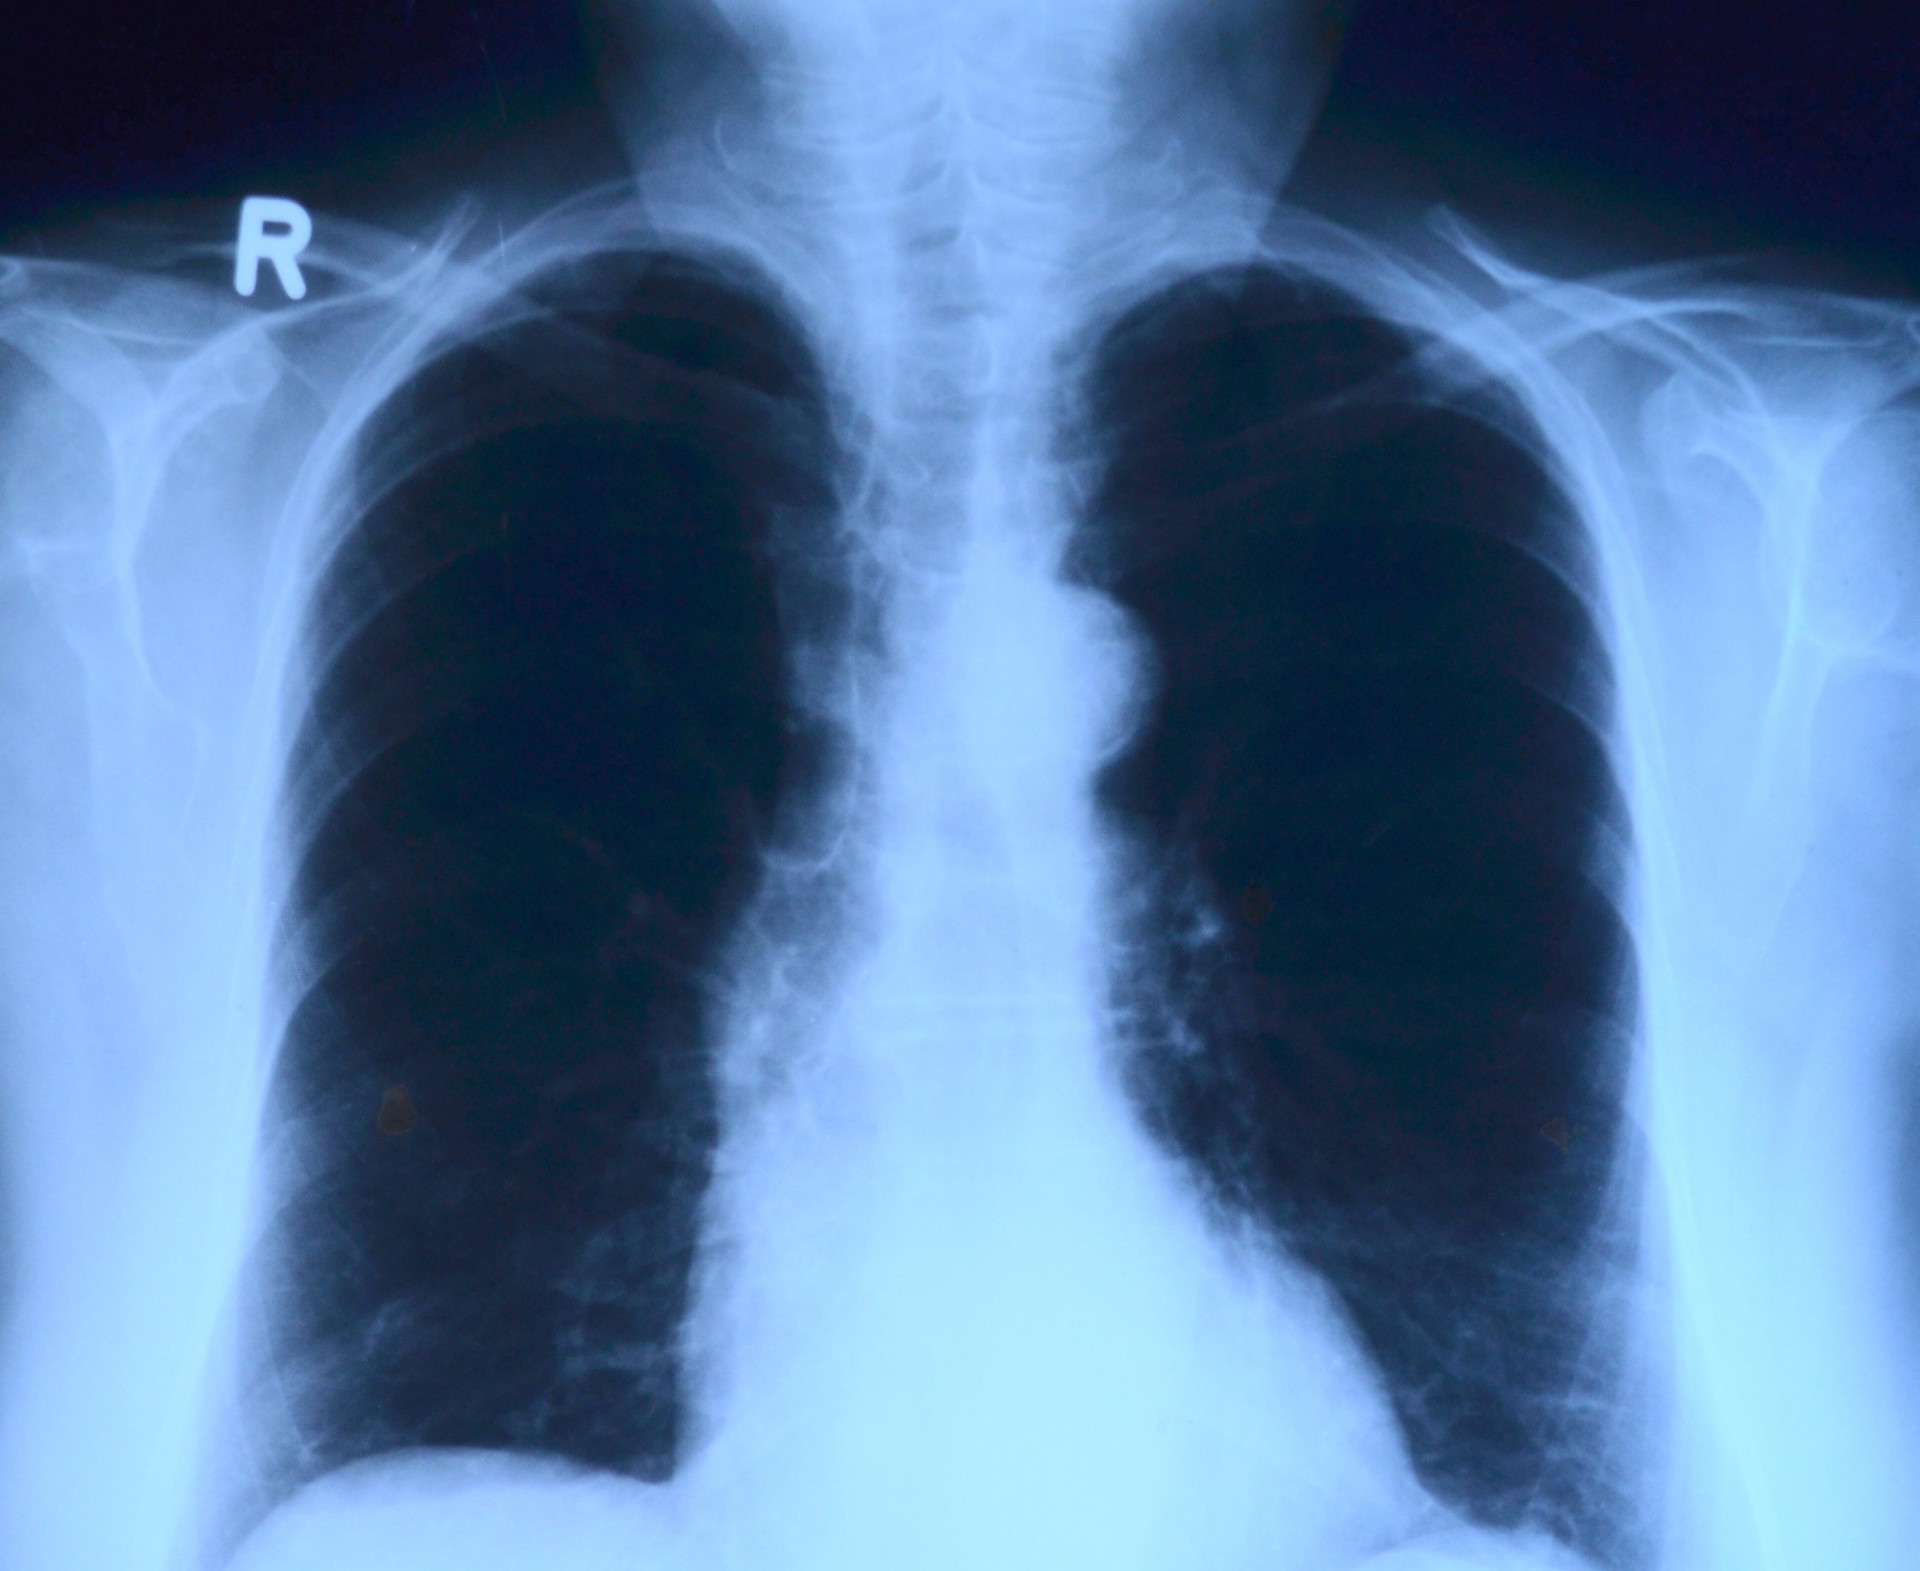

Ставропольское медицинское учреждение занимает первое место среди 72 медицинских учреждений России по объёму выполненных в 2021 году эндоваскулярных вмешательств, связанных с гиперплазией предстательной железы.

Рентгенохирургия развивается в краевой больнице уже 20 лет. Ежегодно здесь обследуются более 5 тысяч пациентов и выполняется не менее 6 тысяч ангиографических исследований и 4,5 тысяч рентгенэндоваскулярных операций.

Справочно: эндоваскулярные операции – хирургические вмешательства, проводимые на кровеносных сосудах чрескожным доступом под контролем методов лучевой визуализации с использованием специальных инструментов.